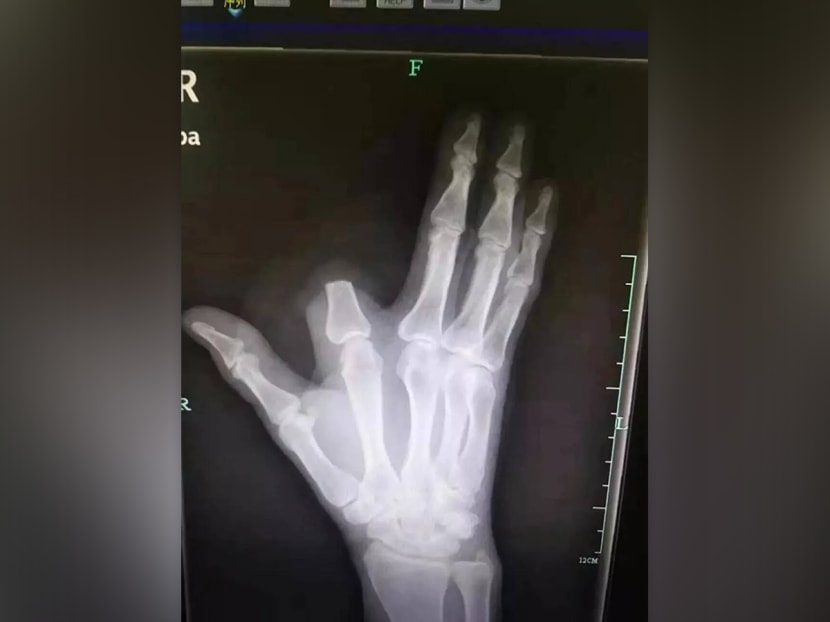

The 60-year-old farmer named Zhang was cutting firewood near his mountain village in the Shangyu district of Zhejiang province when he was bitten on the finger by the snake, Hangzhou Daily reported.

He identified it as a particularly feared type of viper known locally as the “five-step snake” because of the belief that victims will not be able to walk more than five paces before dying, and chopped off the finger to prevent the venom from spreading.

However, he left the amputated finger on the mountainside, which meant doctors would have no chance of successfully reattaching it.

Dr Yuan Chengda, another doctor from the hospital, said it was a pity that Mr Zhang would not be able to have the finger reattached.